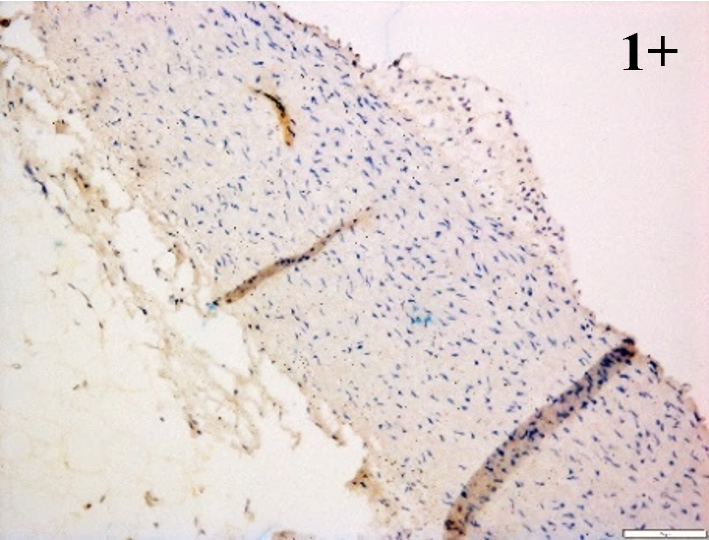

Immunoreactions of ICAM-1, VCAM-1, e-selectin, IL-6, IL-8, NF-

According to the percentage endothelial staining of cells, semi-quantitative

scores were applied. Score: 0 (negative); 1+ (1–10% positive cells); 2+

(11–25% positive cells) and 3+ (